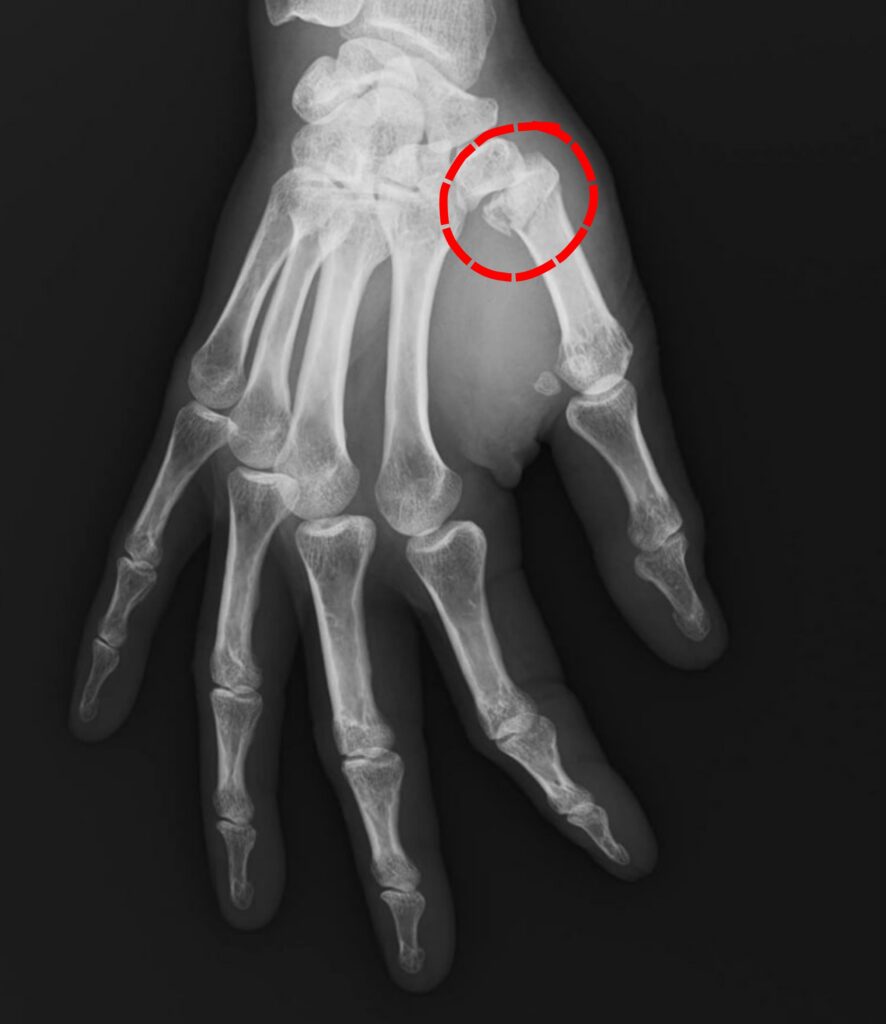

Jeder Finger an der Hand besitzt einen Mittelhandknochen, welcher durch einen Unfall brechen kann. Eine Besonderheit hierbei nimmt der Mittelhandknochen des Daumens ein. Dieser bricht nämlich oft im Bereich der Basis, also handgelenksnahe. Hierbei zeigt er drei so typische Bruchformen, dass diese jeweils einen Eigennamen erhalten haben. Dies wären die Bennett-, die Rolando- und die Wintersteinfraktur. Da es sich fast ausnahmslos um verschobene Brüche handelt, benötigten diese in der Regel eine Operation. Lediglich komplett unverschobene Brüche können mittels einer konservativen Gipsruhigstellung für 5 Wochen ausbehandelt werden.

Bennett-Fraktur

Definition: Intraartikuläre Fraktur an der Basis des 1. Mittelhandknochens mit Abbruch eines Fragmentes und Subluxation durch Zug der Daumenmuskulatur (v. a. M. abductor pollicis longus)

Ursache: Axiale Stauchung des Daumens (z. B. Faustschlag auf Widerstand). Häufig bei Boxern, Kampfsportlern, Skifahrern

Rolando-Fraktur

Definition: Trümmerfraktur der Basis des Os metacarpale I mit Y- oder T-förmiger Gelenkbeteiligung.

Ursache: Starke axiale Gewalteinwirkung mit Rotationskräften, meist schwereres Trauma als bei Bennett-Fraktur, Sehr instabil → häufig operativ zu versorgen

Es erfolgt eine klinische Untersuchung, sowie ein Röntgen, um die Diagnose zu sichern und den Eingriff zu planen. Oftmals wird eine weitere CT oder MRT durchgeführt, um die Frakturanteile genau beurteilen zu können.